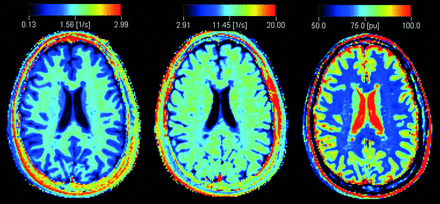

The qMRI sequence yields quantitative maps of R1, R2, and PD (Fig 1), which are used for measurements and to create synthetic images matching the conventional ones (Fig 2). The postprocessing time of the raw image dataset was approximately 1 minute on an ordinary PC by using SyMRI Diagnostic software (SyntheticMR, Linköping, Sweden) to create the synthetic images. Relaxation time values (T-values) were obtained from R1 and R2 by calculating T = 1/R. Using the software MevisLab, Version 2.4 (MeVis Medical Solutions, Bremen, Germany), we anonymized the synthetic images with corresponding conventional images and presented them to a neuroradiologist in random order. For each patient, synthetic T2-weighted, T2-FLAIR, T1-weighted, and T1-weighted Gd images were displayed side by side. MS lesions were identified by conventional neuroradiologic criteria, described in the McDonald criteria for MS. The MS lesions were then classified by visual assessment as enhancing or nonenhancing. The neuroradiologist had access to the conventional images for confirmation of the findings (Fig 3A).

An example of quantitative R1 (left), R2 (middle), and proton density (right) maps derived from the qMRI scan in a patient with MS.